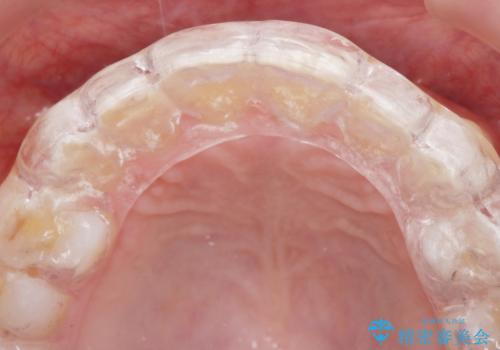

歯ぎしりや歯の保護のためにナイトガードを作製しました。

ナイトガードは歯の保護だけではなく、矯正治療後の歯の後戻りの防止もしてくれます。